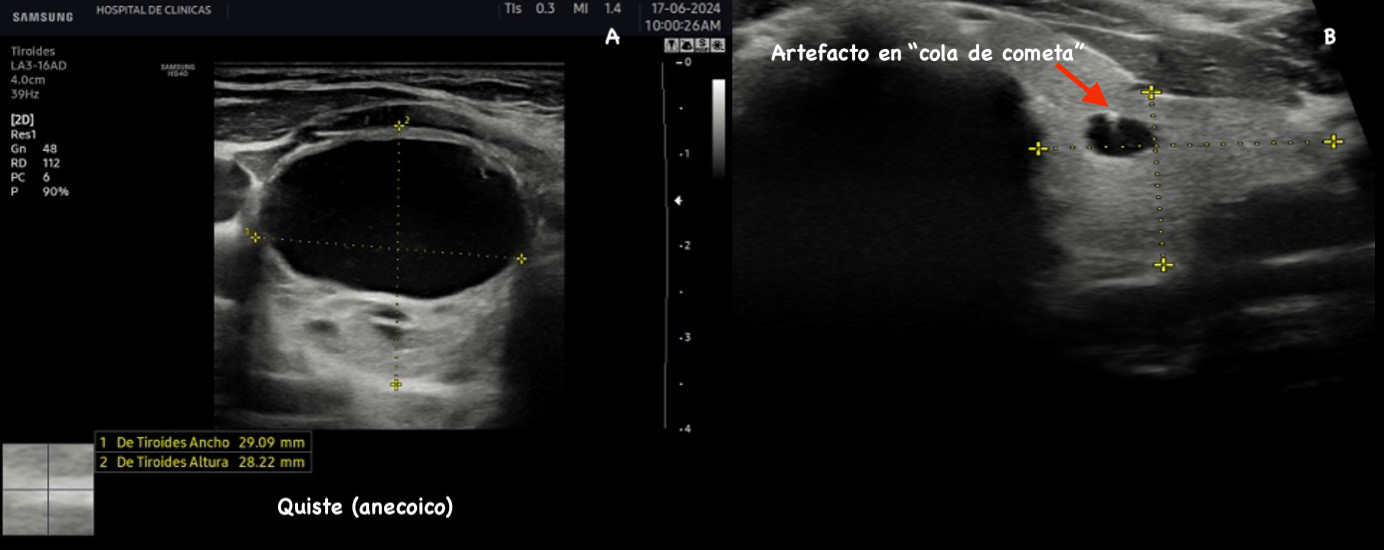

Figura 7: Cortes transversales de quiste tiroideo y microquiste con “artefacto en cola de cometa”(flecha).